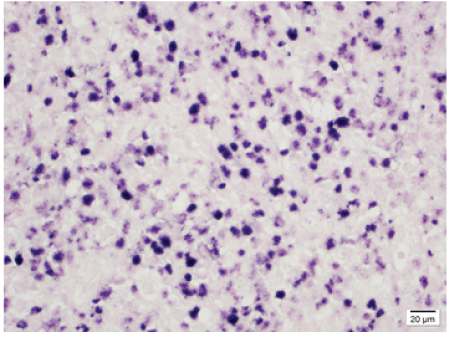

2016年11月初,患者在第二次初级保健医生就诊后的一天内前往当地牙医诊所就诊。进行了全面的临床评估和影像学检查(图1)。患者没有出现面部不对称或面部皮肤变化。口腔内检查显示口腔黏膜正常完整,口腔内结构解剖正常。刺激后上颌后左象限牙齿热测试结果为阴性,叩诊测试结果为非局部性轻度压痛。患者牙周健康,口腔卫生良好。除上颌左第二前磨牙根无症状保留外,临床上无明显龋损(#13)。矫形断层扫描显示双侧上颌窦无浑浊,上颌牙槽骨水平在正常范围内,冠状面内没有显示龋病或相关的根尖周放射透度。根尖解剖正常,无吸收、扩口或移位。x线片上发现残留根#13,根尖周无相关的放射透光度

图1:前处理矫形图显示清晰的上颌窦,在左上颌后牙槽骨段无骨透光性。冠内或根尖周无放射透光度。牙槽骨水平在正常范围内。

在组织学上证实为高度怀疑淋巴结外NK/ t细胞淋巴瘤后,患者转至当地医院进一步检查并提出治疗建议。由于他呈现的症状的复杂性,他的护理被转到德克萨斯州休斯顿的MD安德森癌症中心,在白血病/淋巴瘤科进行多学科管理。进一步的手术活检和免疫组化检测证实淋巴瘤和原位杂交eb病毒编码RNA(图3)在恶性细胞中呈阳性,证实了结外NK t细胞淋巴瘤(鼻型)的诊断。

图3:病理切片显示EBER阳性NK/ t细胞。